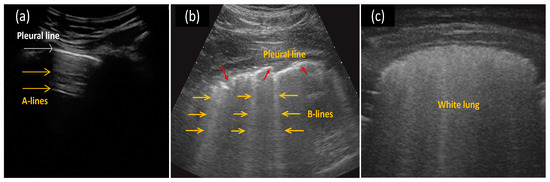

2.2. LUS Image Features for COVID-19 Pneumonia